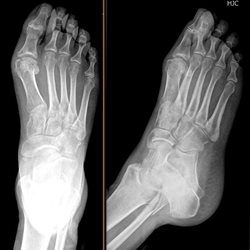

Adult Extremities 5

Various foot cases